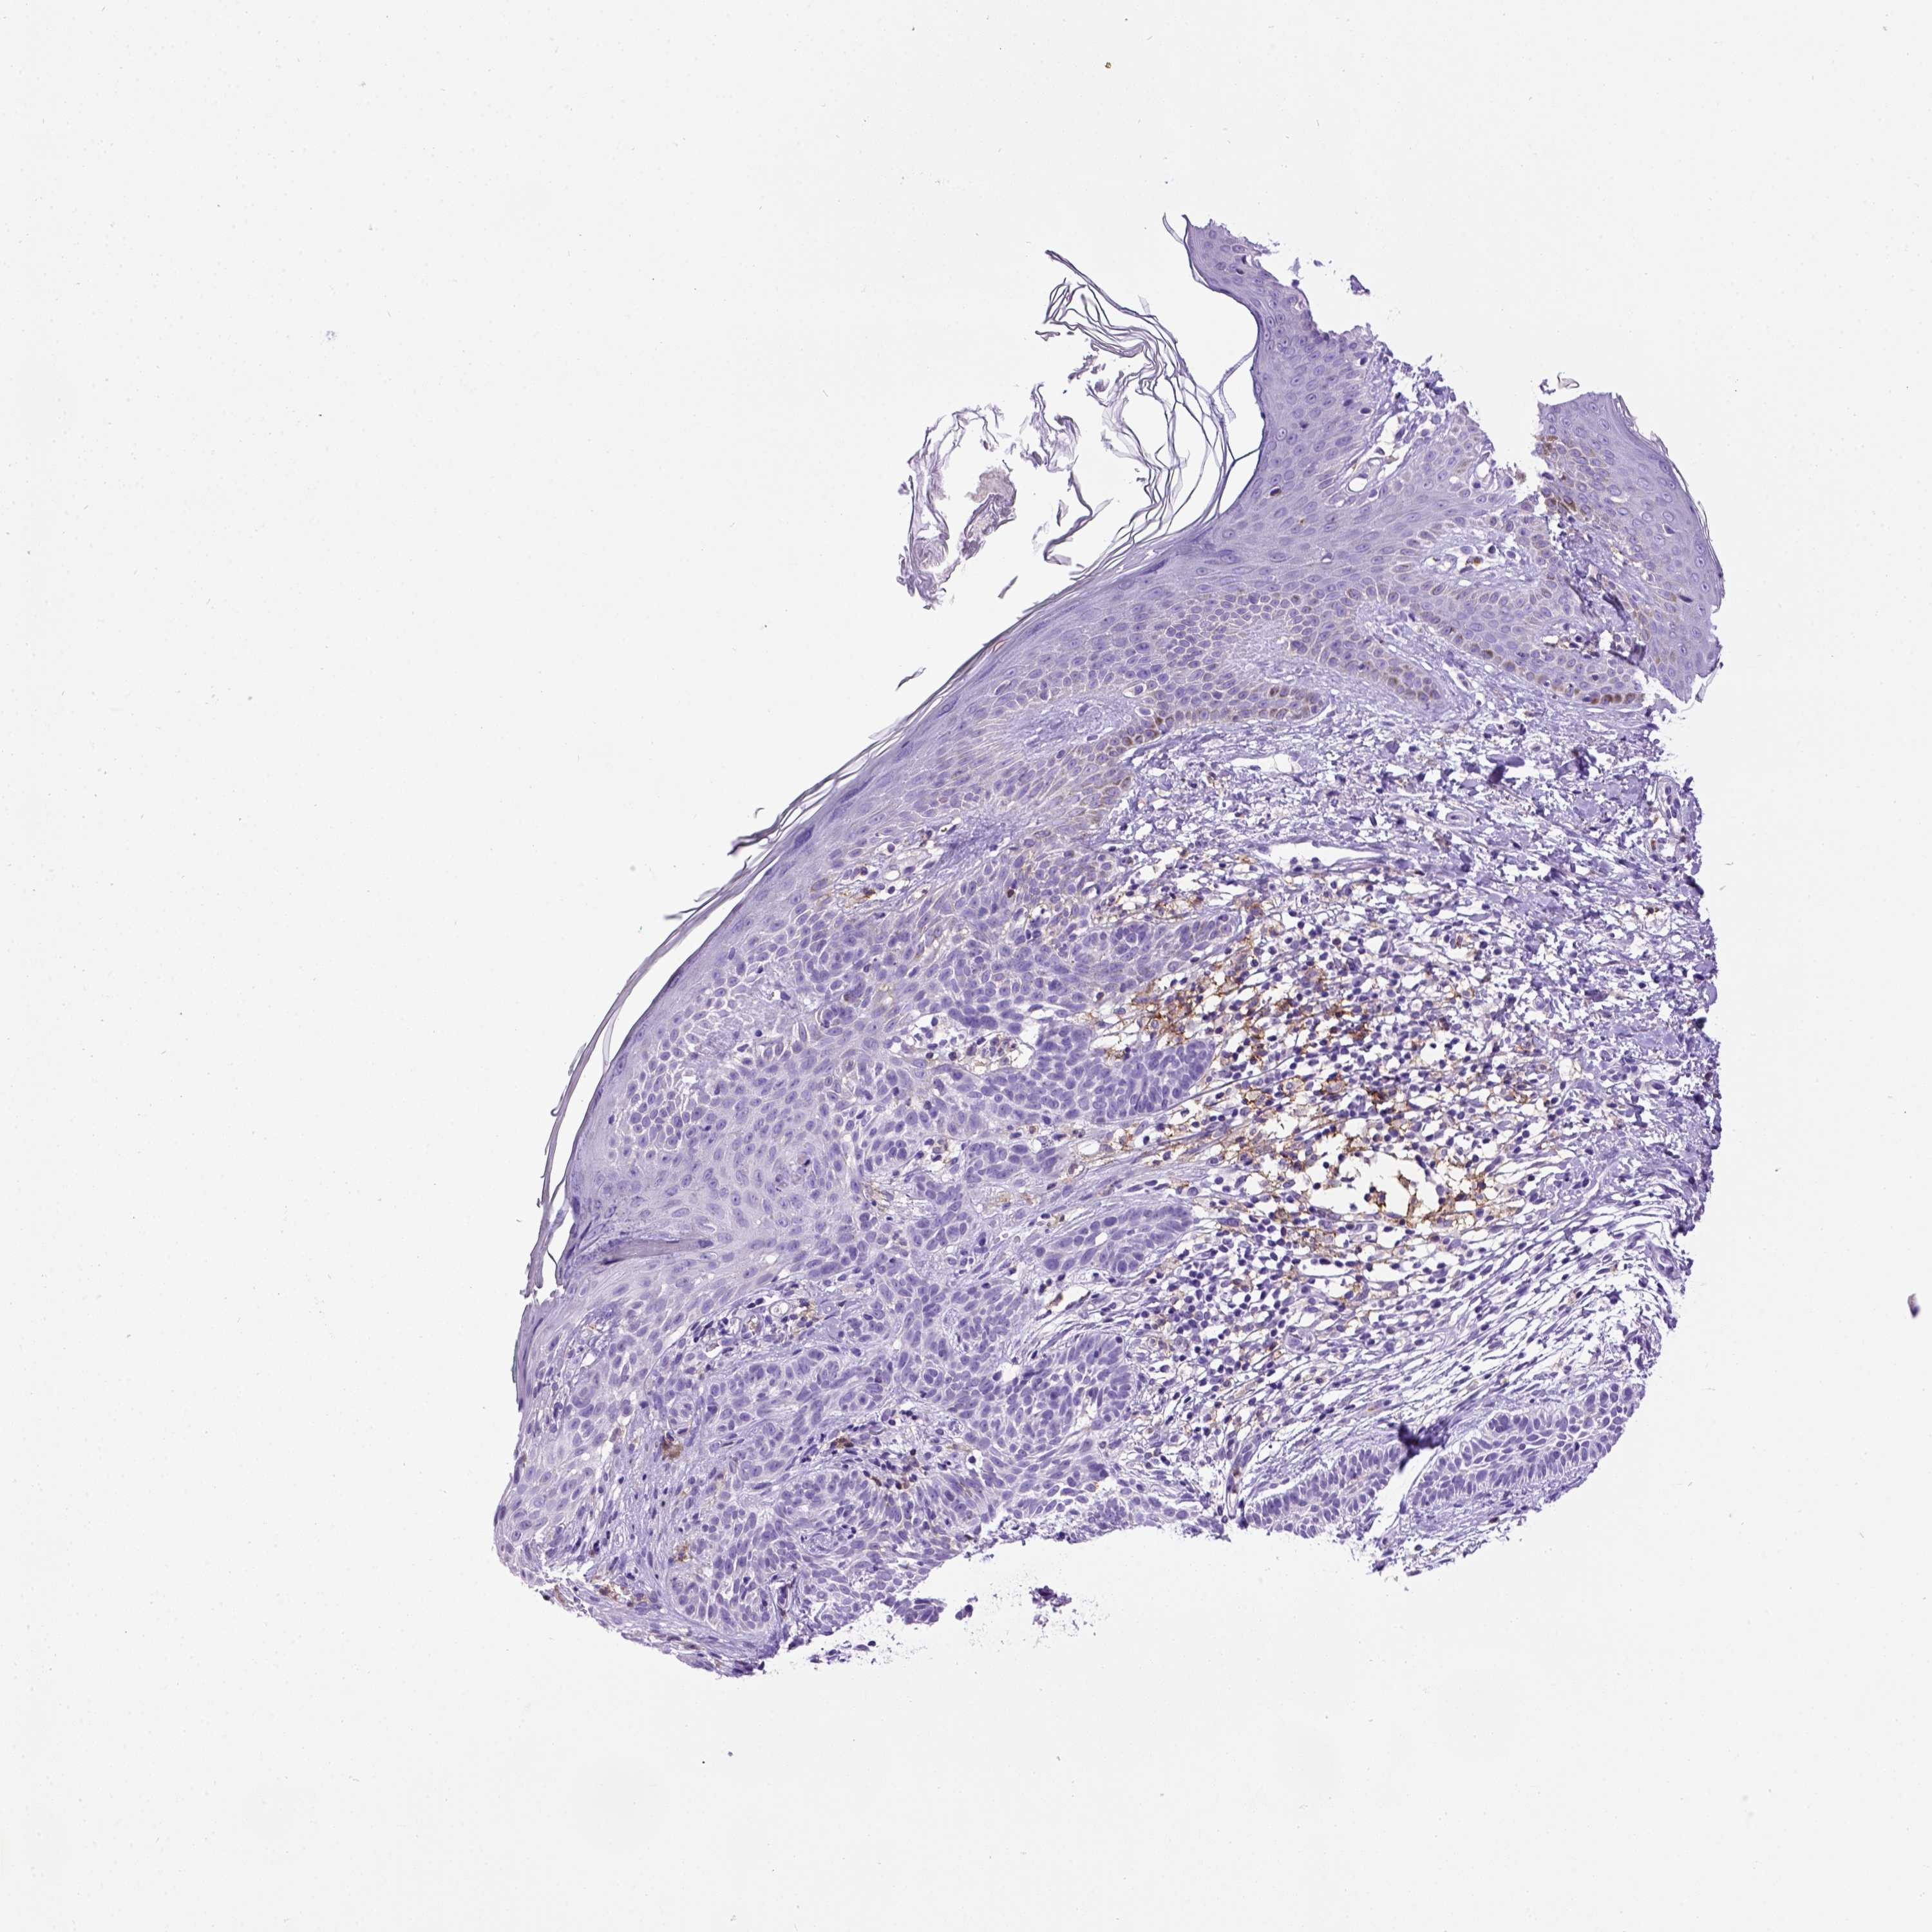

CANCER SKIN CANCER Show tissue menu

Basal cell and squamous cell cancer

SKIN CANCER - Protein expressioni

A mouse-over function shows sample information and annotation data. Click on an image to view it in a full screen mode. Samples can be filtered based on level of antibody staining by selecting one or several of the following categories: high, medium, low and not detected. The assay and annotation is described here.

Each image is clickable and will lead to virtual microscopy that enables deeper exploration of all samples and also displays staining intensity scores, fraction scores and subcellular localization as well as patient and tissue information for each sample.

Antibody CAB072871

Squamous cell carcinoma, NOS

Basal cell carcinoma